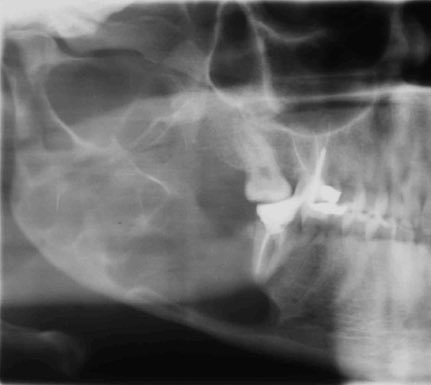

Odontogenic keratocyst (OKC)

قد يكون هذا من اكثر امراض الفك فيه اختلاف وجهات نظر وخيارات علاج متعددة وقد تغير اسمه مرتين عبر العقود الماضية. ولعل اكثر ما يميزه عن باقي تكيسات الفك هو كثرةعودة التكيس في الفك بعد علاجه اذا تم علاجه بالطريقةالتقليدية لتكيسات الفك باستئصاله فقط

OKC

تتراوح نسبة تكونه مرةأخرى بعد الاستئصال في الدراسات من٥-٥٠٪،وبالتالي يقتضي أن يتم تشخيصه اولا بشكل صحيح عن طريق خزعة وتقرير من قبل طبيب امراض الفم،وايضاعلاجه يقتضي إجراءات إضافيةبعد استئصاله من الفك لتقليل نسبةتكونه مرة أخرى

عادةيتم تشخيصه في مرحلةعمرية مبكرة(١٠-٤٠ عام)